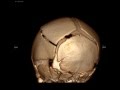

RSV Bronchiolitis Subpleural Consolidation on Mindray TE-X linear array transducer lung preset

6 m.o. Boy RR 40s, subcostal retractions with head bobbing, RSV pcr positive. Lung US using Mindray TE-X linear array transducer detects subpleural consolidation.

Images captured with Mindray TE-X, linear array transducer on lung preset.